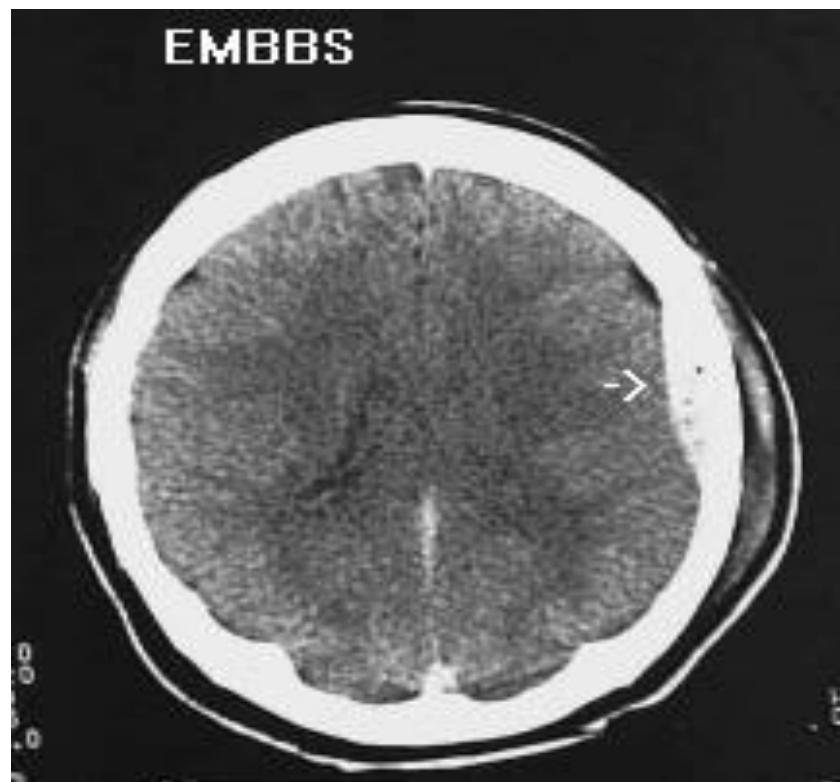

Epidural Hematoma

- Diagnosis: Epidural Hematoma.

- CT Finding: Biconvex (Lens-shaped) hyperdensity; does not cross suture lines.

- Pathology: Usually arterial bleed (Middle Meningeal Artery).

- Note: May show midline shift.